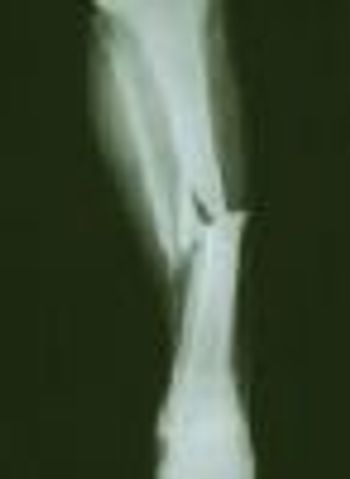

The use of tramadol in older patients is associated with a higher risk of hip fracture compared with the use of codeine or commonly used nonsteroidal anti-inflammatory drugs (NSAIDs), say researchers recently writing in in the Journal of Bone and Mineral Research.